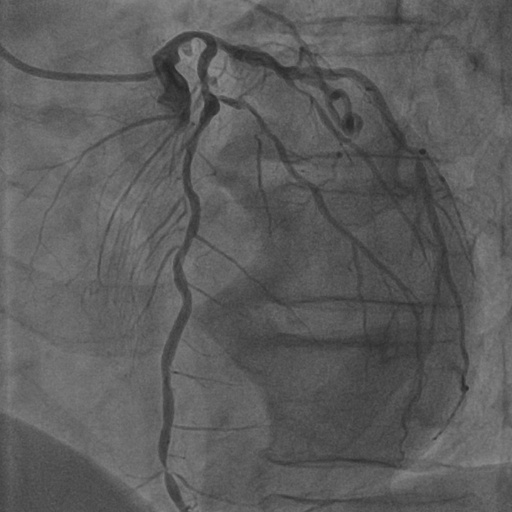

Hessian prior loss .

To test the effect of the Hessian prior loss, we remove the Hessian prior loss. As a result, the segmentation performance, as shown in Table 2, also decreases the Dice score by 0.0063. The comparison between the without and with is shown in Figure 8 (b), where the orange area indicates the difference between them. The zoom-in patch shows that our model predicts less noticeable vascular regions incorporating the Hessian prior loss .